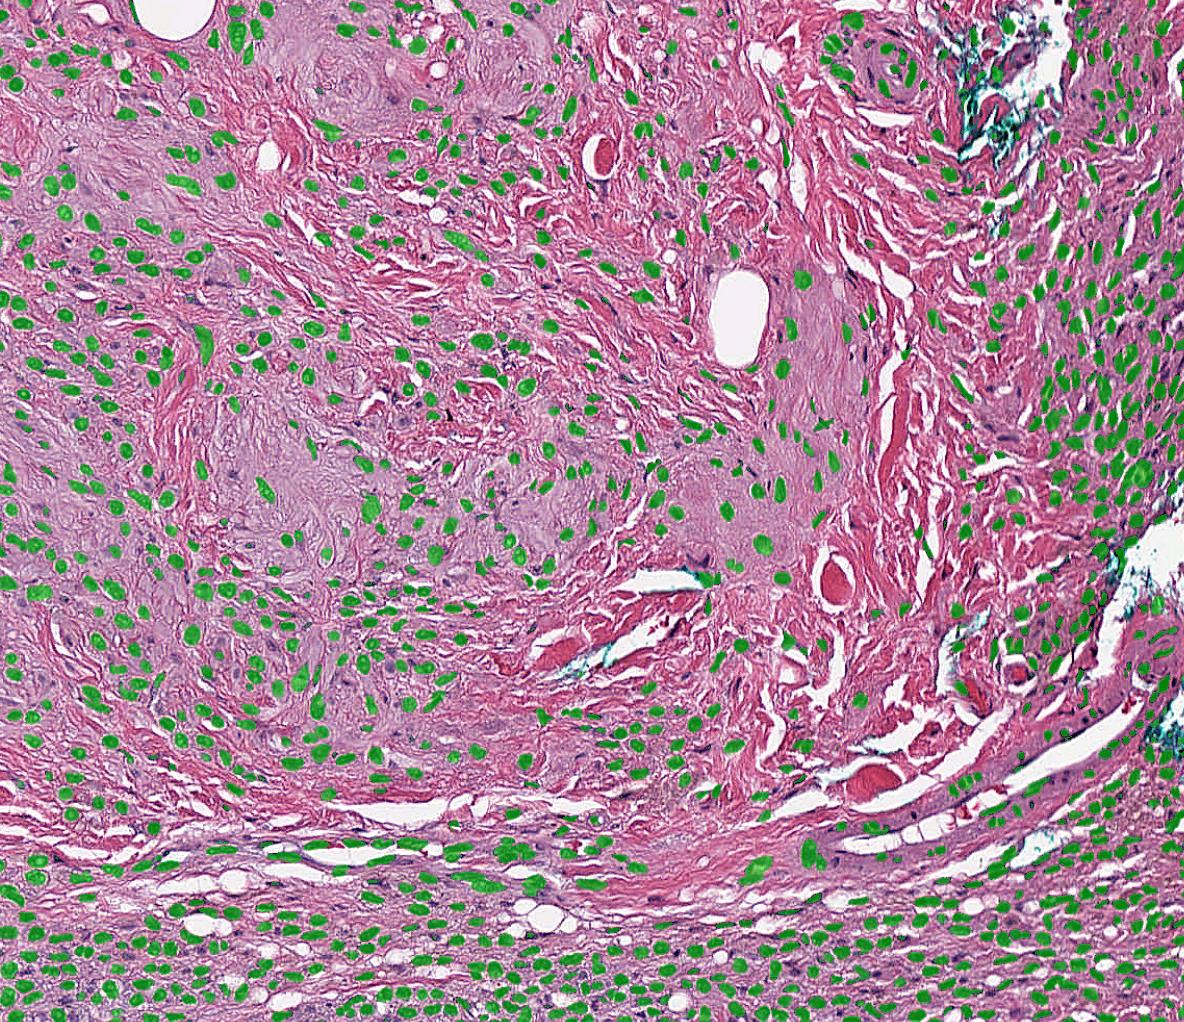

FAST is an open-source framework developed by researchers at the Norwegian University of Science and Technology (NTNU) and SINTEF. The main goal of FAST is to make it easier to do high-performance processing, neural network inference, and visualization of medical images utilizing multi-core CPUs and GPUs. To achieve this, FAST use modern C++, OpenCL and OpenGL, and neural network inference libraries such as TensorRT, OpenVINO, TensorFlow and ONNX Runtime.

• Deep learning – FAST provides a common interface for neural networks supporting different model formats (ONNX, protobuf, SavedModel, OpenVINO, UFF) and backends (Google TensorFlow, NVIDIA TensorRT, Intel OpenVINO, Microsoft ONNX Runtime), making it possible to create real-time neural network pipelines.

• Fast concurrent visualization – Rendering and computation are done in separate threads to ensure smooth responsive visualizations. Several types of visualizations are supported both 3D (mesh, point, line, image slice and volume rendering) and 2D (2D image, image slice and segmentation/label rendering, whole slide image (WSI) pyramids).